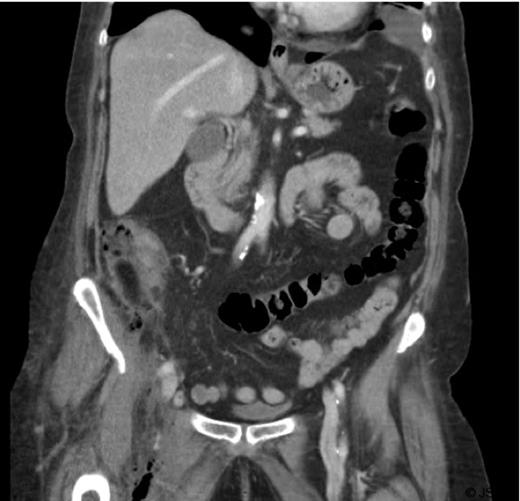

A 75- year old female was admitted as an emergency with right iliac fossa pain. She was afebrile. Bloods on arrival showed leukocytosis of 18.6 and CRP of 235.5. Clinical examination was inconclusive. During her over-night stay, she developed tachycardia and hypotension which responded to fluids. On review, abdominal examination revealed fullness in the right iliac fossa. More importantly she developed swelling and redness of the right thigh. The patient had a CT abdomen, pelvis and upper thigh that showed gas containing fluid collection in the right iliac fossa in keeping with either diverticular or appendicular abscess (Figure 1). It also showed inferior extension of the gas into the right ilio-psoas muscle, groin and upper thigh (perivascular) raising the possibility of necrotising fasciitis (Figure 2).